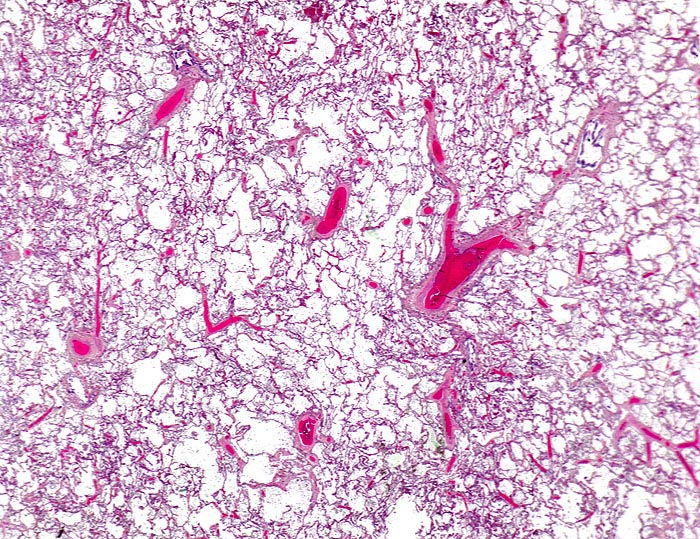

In einer frühen Phase kommt es zur roten Stauungsinduration, welche in eine braune Stauungsinduration übergeht. Die Eindrückbarkeit der Lungen ist aufgrund der Fibrosierung der Alveolarsepten vermindert. Die meist fleckförmige braune Verfärbung beruht auf der Anhäufung von hämosiderinhaltigen Herzfehlerzellen in den Alveolarlichtungen. Makrophagen in den Alveolarlichtungen phagozytieren die ausgetretenen Erythrozyten. Der Nachweis von Erythrozyten im Zytoplasma von Makrophagen spricht für eine frische Blutung. Nach 3-5 Tagen ist in den Makrophagen Hämosiderin nachweisbar. Das Hämosiderin lässt sich mittels Eisenfärbung (Berliner-Blau) zuverlässig von Staubpigment abgrenzen. Als sicheres Zeichen für eine ältere Blutung gelten >20% hämosiderinspeichernde Makrophagen in der bronchoalveolären Lavage (BAL). Die hämosiderinhaltigen Alveolarmakrophagen werden auch Herzfehlerzellen genannt, da sie gehäuft im Rahmen einer linkskardialen Stauung bei Mitralklappenstenose auftreten.

Aufgrund des erhöhten Druckes in den Lungenkapillaren kommt es zur sekundären Pulmonalarteriensklerose. Die Befunde an den Pulmonalarterien sind bei primärer und sekundärer pulmonaler Hypertonie prinzipiell gleich. Die Pulmonalarterienhauptstämme zeigen Atherombildungen (> 3698) (> 3589) und eine Mediafibrose. Die elastischen Pulmonalarterienäste entwickeln atheromatöse Polster, welche makroskopisch als gelbe Flecken erkennbar sind. Ulzera oder Verkalkungen wie in den Arterien des grossen Kreislaufes werden jedoch kaum beobachtet. Die Veränderungen an kleineren muskulären Arterien (Mediahypertrophie, zelluläre Intimaproliferation, Intimafibrose, Wandnekrosen bei sehr hohen Drücken) und Venolen (Venulosklerose) sind nur histologisch nachweisbar.

Morphologische Merkmale:

• Mediahypertrophie der Pulmonalvenen.

• Fibrosierung und Verdickung der Alveolarsepten.

• Siderinhaltige Alveolarmakrophagen (=Herzfehlerzellen).